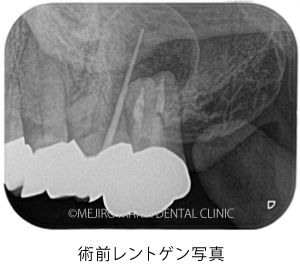

本症例の患者様は、左上7番(第2大臼歯)の歯ぐきから膿が出ており、来院されました。口腔内を確認すると根尖性歯周炎(※1)が原因で、左上7番根尖部(歯の根の先)に、瘻孔(フィステル・サイナストラクト ※2)が確認できました。CTにて膿が出ている箇所(写真の赤矢印)を確認すると、左上7番の根尖部に大きく広がっている病変(写真の赤丸)へ繋がっていることが分かりました。